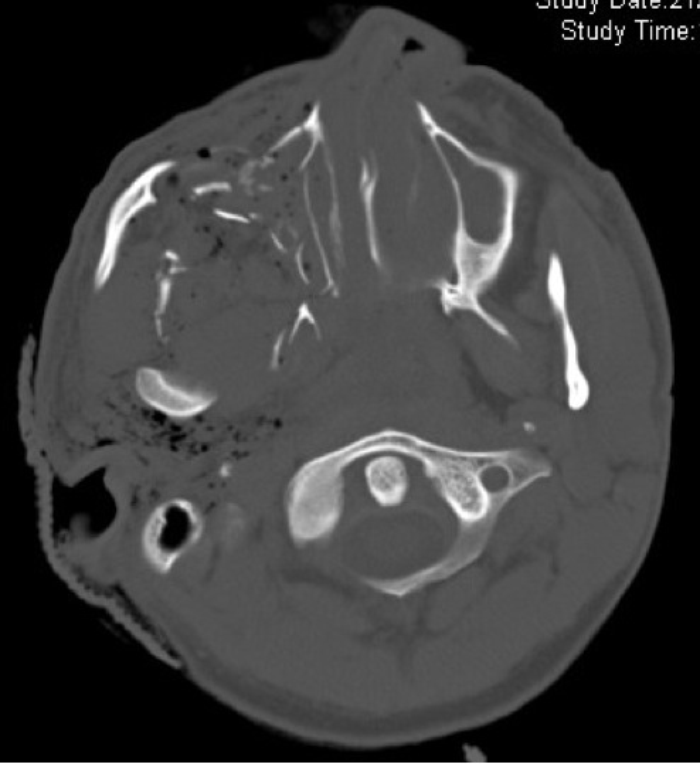

Figure 3: Axial CT scan illustrating a penetrating injury involving the maxilla and temporal bone.

Extensive soft tissue injury, typical of penetrating trauma, below the skull base and associated surgical emphysema is seen.

While this classification is still valid for blunt injuries, the complex injury pattern of penetrating wounds, especially gunshots, requires more detailed description. The complications of bullet (or other penetrating missile) injuries will depend to an extent on the velocity of the projectile. High velocity weapons generally travel in a straight line, and cause the majority of damage via direct injury, cavity formation, heat or bone fragments. Low velocity bullets, however, may be more easily deflected by bone and therefore travel a more unpredictable path, causing extensive damage to soft tissue structures (Figure 3).